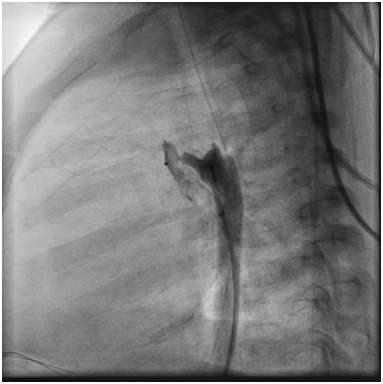

Angiography at the beginning of the cath showed that the PDA had completely disappeared (Figure 3).

Figure 3 Angiogram in the Aorta showed that the PDA disappeared.